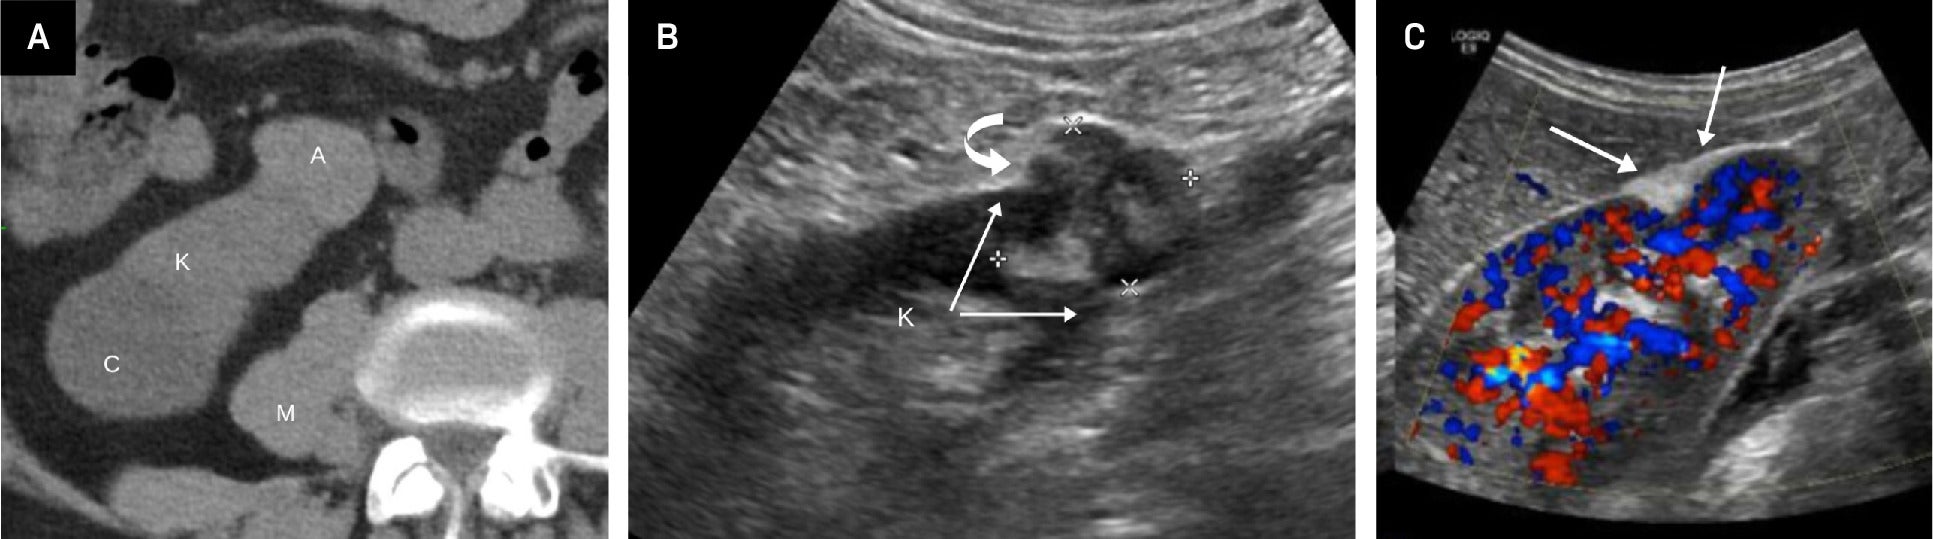

Fat-poor angiomyolipoma (fpAML) with angular interface. CT scan (A) showing the right kidney [K] with a simple cyst [C] and a fpAML [A]. The Hounsfield unit of the fpAML was 50 and identical to the HU of the adjacent muscle [M]. US showed this fpAML (B) to have mixed echogenicity, with an angular interface (arrows) and some overflow of the renal cortex (curved arrow, K = kidney). US of peripheral AMLs (C), which, like fpAMLs, often have the “overflowing beer” sign (arrows) with the renal cortex. The presence of either an angular interface or “overflowing beer” sign is helpful in distinguishing fpAMLs from renal cell carcinomas.

As we discussed more extensively in Part I, morphological features help distinguish classic AML from RCC on US, and they can similarly aid in differentiation of fpAML.1 Kim et al found that on contrast-enhanced CT of renal masses <4 cm, an angular interface had a sensitivity of 55% and specificity of 81.9% for fpAMLs, while the “overflowing beer” (also referred to as the “drooping”) sign carries a sensitivity of 61% and specificity of 97.10 Strother et al demonstrated that both signs were strongly associated with fpAML, with odds ratios of 12.6 and 11.2, respectively ( Figure 1 ).11 Thus, when an angular interface or overflowing beer sign is present, the lesion is more likely an AML than RCC.